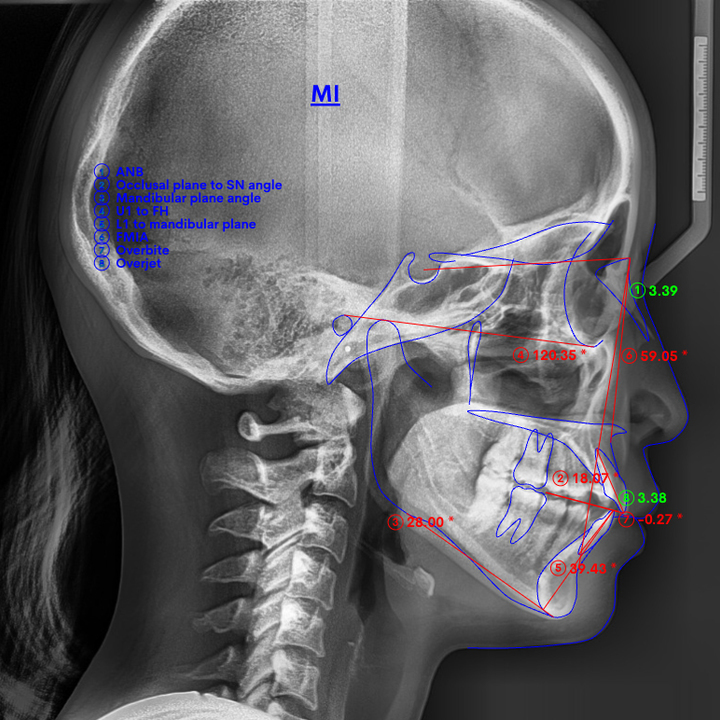

では、出っ歯を改善するにはどれくらい引っ込めればいいのか。横顔の変化を実感できるのは、最低でも前歯が4〜5mm引っ込んだとき。重度の出っ歯なら、7〜8mmは必要です。

先ほどご説明した通り、小顔で顎が小さい方はスペースが足りません。そこでスペースを確保するために、前歯しか動かせない格安矯正でよく用いられるのが、拡大床という治療法です。

ネジの力を利用して歯を外側へ押し広げることで、前歯を並べるスペースを確保します。

ただ拡大床は、歯列を広げすぎないよう細心の注意を払う必要がある、とても難しい治療法

経験不足の歯科医師では、過度に歯を押し広げてしまい、出っ歯かえって酷くなることがあります。

上記のような失敗を起こさないために当院では、奥歯奥側移動してスペースを確保できるマウスピース矯正「インビザライン」をおすすめしています。

その点インビザラインでは、親知らずを抜いたスペースに一番奥の歯を動かします。

それにより空いたスペースに次の奥歯を動かし、さらに次の奥歯を動かします。

こうして順繰りに奥へと歯を移動させることで、4〜5mm以上のスペースを確保して、前歯をきれいに並べられるのがインビザラインの優れたポイント。

この方法なら親知らずを抜いた広いスペースを利用できますから、あごが小さくて出っ歯でお悩みの患者さまでも治療可能です。